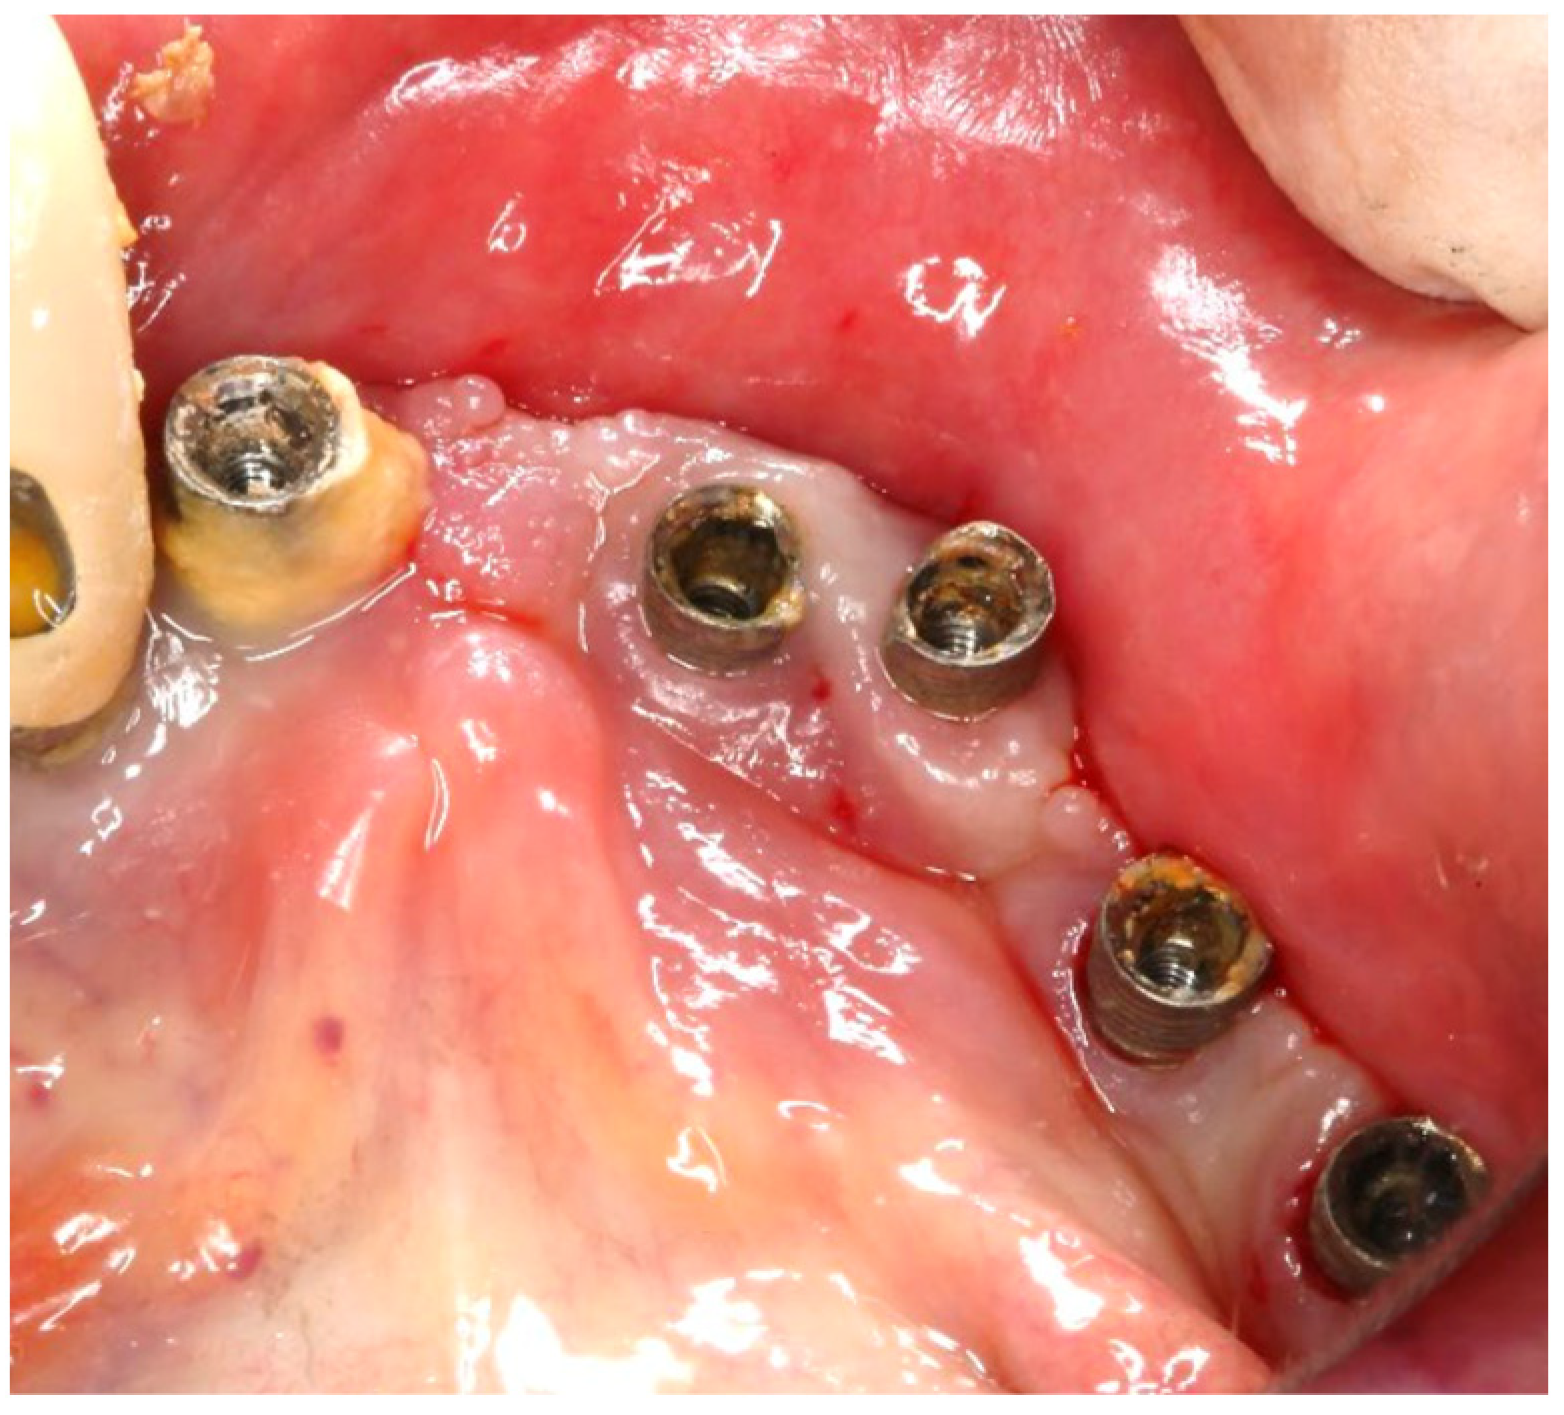

A 75-year-old male patient presented to the private clinic (Tel Aviv-Yafo, Israel) with severe pain, swelling, bad odor, and suppuration localized in the lower right posterior region (Figure 6). The chief complaint indicated discomfort and functional impairment related to that site. The implants placed in the first and second lower right molar region presented severe and vertical bone loss. The patient was a heavy smoker, 2–3 packs/day for 50 years, but quit smoking 5 years ago. Systemically, the patient had diabetes mellitus, controlled with daily insulin (HbA1C between 6% and 7%); osteoporosis, managed with bisphosphonates (via oral, around 2 years); and a cardiovascular condition, requiring anticoagulant therapy (more than 5 years).

The intraoral examination revealed poor oral hygiene, characterized by significant plaque accumulation (over 65% plaque index) along the gingival margins and interdental areas. The periodontal status evidenced a progressive periodontal disease, with bleeding on probing (BoP) over 60%, mainly around all dental implants; peri-implant tissues possessed a high level of inflammatory condition, with localized swelling, high level of BoP, redness, and suppuration at the site of teeth #46 and #47, indicating local acute inflammation. The probing depth (PD) at site implant #46 exceeded 9 mm at both the mesial and distal sites, and at #47, the mesial site had a PD of 7.8mm, while the distal site showed lower bone loss (Figure 7).

The surgical step began with local anesthesia (Lidocaine 2% with 1:100,000 epinephrine—Henry Schein Inc., New York, NY, USA) locally administered; the screw-retained crowns on the implants were removed to facilitate proper surgical access (Figure 9). The surgical site was assessed in order to provide a minimally invasive buccal flap design, which was favorable in this case, as it effectively executed the Quadrant protocol.

Figure 6. Initial clinical assessment of sites #46 and #47.